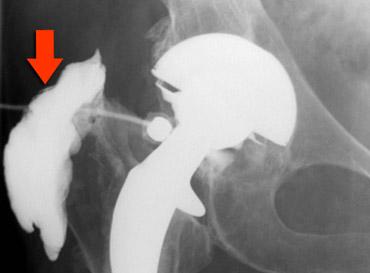

Tràn xi măng ra ngoài

Khi ổ cối được chuẩn bị để đặt cốc, có thể xảy ra thủng. Khiếm khuyết này được lấp đầy bằng mảnh xương, xi măng hoặc ghép xương.

Tràn xi măng ra ngoài thường không có triệu chứng.

Các biến chứng hiếm gặp bao gồm rò ruột, bao bọc các cấu trúc mạch máu thần kinh và bỏng thành bàng quang.